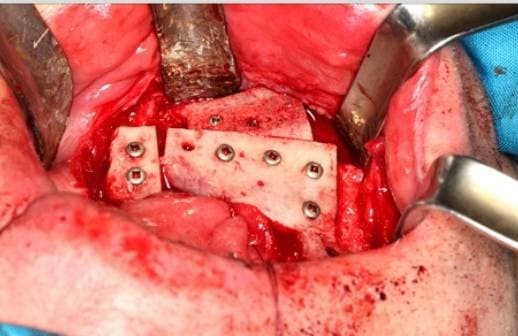

После стабилизации по вертикали пошли на горизонтальное увеличение кости. Здесь нам нужно куда больше материала, чем может обеспечить естественная генерация клеток организмом пациента, и перемещением имеющихся костей черепа не обойтись. Мы принимаем решение отпилить пациенту кусок таза и сделать аутотрансплантат, то есть найти не очень нужный кусок кости и пересадить его в то место, где он нужнее.

Не то, чтобы в организме у человека есть совсем уж ненужные кости, но некоторые можно чуть подпилить. И лучше всего для наших целей подходит подвздошная кость — это стандартная кость, которая используется для такого типа переносов ткани. Конкретно ткань берётся с гребня.

Операция проводится так: пациент засыпает, за него берётся одна бригада снизу и одна бригада сверху. То есть мои коллеги открывают пациента в области таза и пилят кость, а я готовлю ложе для аутотрансплантата. Между отпиливанием куска пациента и прикручиванием винтами этого куска в другое место пациента происходит его формирование. Конкретно на этой операции работало 3 хирурга и ассистенты.

Вот что достали из недр организма пациента мои коллеги: